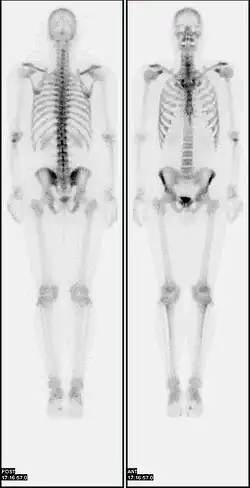

In a typical bone scan technique, the patient is injected (usually into a vein in the arm or hand, occasionally the foot) with up to 740 MBq of technetium-99m-MDP and then scanned with a gamma camera, which captures planar anterior and posterior or single photon emission computed tomography (SPECT) images.[19][14] In order to view small lesions SPECT imaging technique may be preferred over planar scintigraphy.[20]

In a single phase protocol (skeletal imaging alone), which will primarily highlight osteoblasts, images are usually acquired 2–5 hours after the injection (after four hours 50–60% of the activity will be fixed to bones).[19][14][21] A two or three phase protocol utilises additional scans at different points after the injection to obtain additional diagnostic information. A dynamic (i.e. multiple acquired frames) study immediately after the injection captures perfusion information.[21][22] A second phase "blood pool" image following the perfusion (if carried out in a three phase technique) can help to diagnose inflammatory conditions or problems of blood supply.[23]